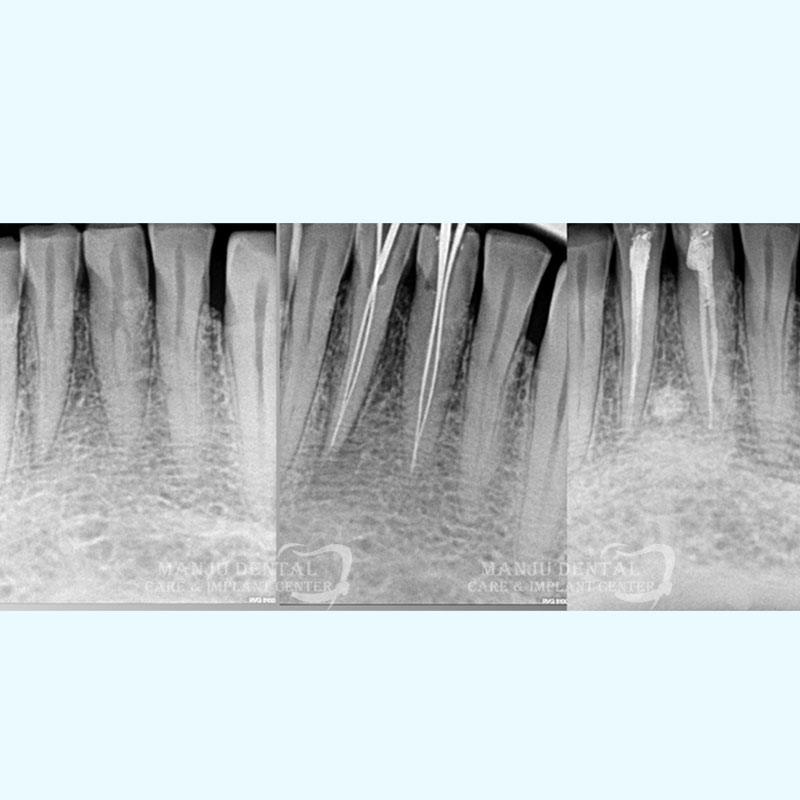

8 Years Successful Outcome Of Endodontically Managed Two Canalled Lower Anterior

1.  After clinically examining the tooth, a radiograph is done using x-rays and  local anaesthesia is administered to make tooth numb. An assess opening is done to enter pulp chamber and very small instruments are used to clean the pulp from the chamber and root canals of the tooth.

2. After the space is cleaned and shaped, the root canals are filled with a biocompatible material called gutta-percha. The gutta-percha is placed with a endodontic sealer to ensure complete 3D obturation of the root canal system. After obturation a permanent restoration is done to completely seal the tooth.